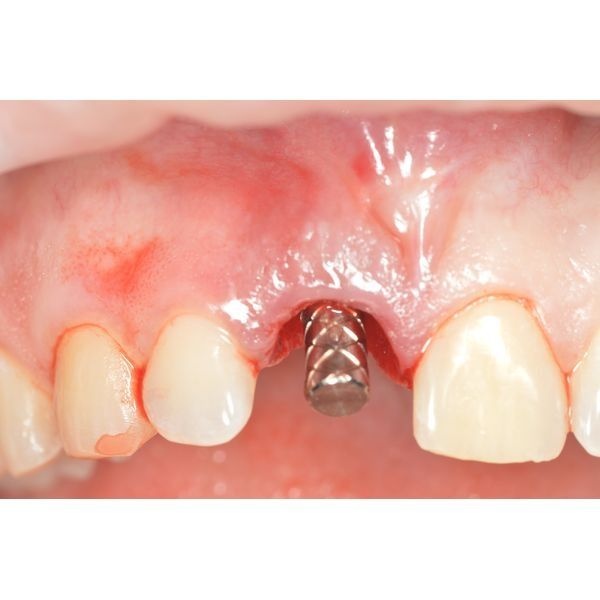

Под местной анестезией удалили зуб, после чего сформировали ложе для имплантата и провели пластику мягких тканей вокруг него. Изготовили и установили временную коронку на 4 месяца.

Через неделю после операции сняли швы. Спустя месяц провели контрольный осмотр. Протезирование запланировали примерно на 3–6-й месяц после хирургического вмешательства, точный срок зависел от приживления имплантата.